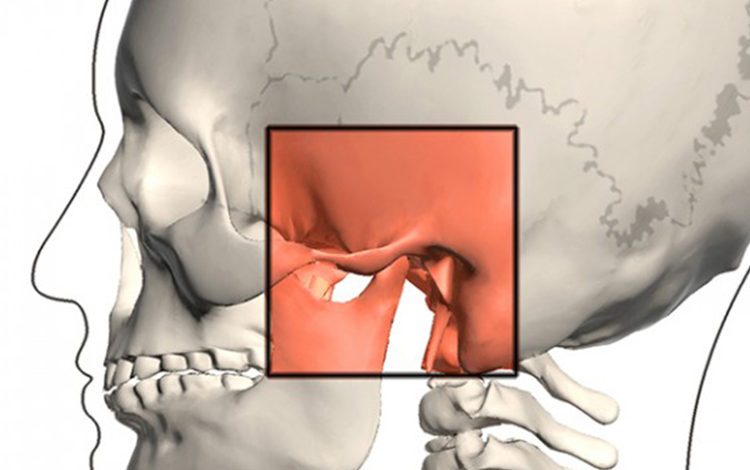

Estetik Plastik ve Rekonstrüktif Cerrahi Uzmanı Op. Dr. Diren Çelik, çene problemlerine dikkat çekerek, “Çene ucu çıkıklığı (projeksiyonu) normalden az olduğu görülen ve çene ucunun biraz ileri alınması ile estetik olarak fayda sağlanabileceği düşünülen hastalara çene ucu dolgusu yapılabilir” dedi.

Özellikle tüm çene kemiği deformasyonları veya anomalilerine bağlı olarak ısırma bozukluğu olan hastalarda çene dolgusu görüntü olarak fayda sağlasa dahi ısırma bozukluğunu düzeltmeyeceğini ifade eden Op.Dr.Diren Çelik, “Bu tür beklentileri olan hastalarımız için cerrahi müdahele gerekli olacaktır. Burun ameliyatları estetik cerrahinin en sık yapılan ameliyatlarıdır. Bu ameliyat sırasında, nefes alma konusunda iyileştirmek amacıyla bir grup kıkırdak çıkarılmaktadır. Bu kıkırdakların bir kısmı greft olarak burun içerisinde kullanılırken diğer kısmı atılmaktadır. Çene ucunda uzatma düşündüğümüz hastalarda bu kıkırdak dokularını çok küçük parçalar haline getirip, istediğimiz şekle soktuktan sonra çene ucuna yerleştirebiliriz. Bu işlem sonucunda ulaşılacak sonuç kalıcı olacaktır.” şeklinde konuştu.